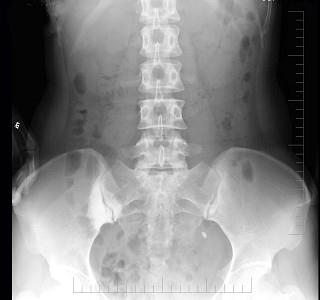

问题 女,26岁,骶髂部疼痛2年余,间歇发作,请结合所提供图像,选择最佳答案 ( )

选项 A、强直性脊柱炎 B、骶髂关节退行性变 C、化脓性髂骨炎 D、结核性髂骨炎 E、致密性髂骨炎

答案 E